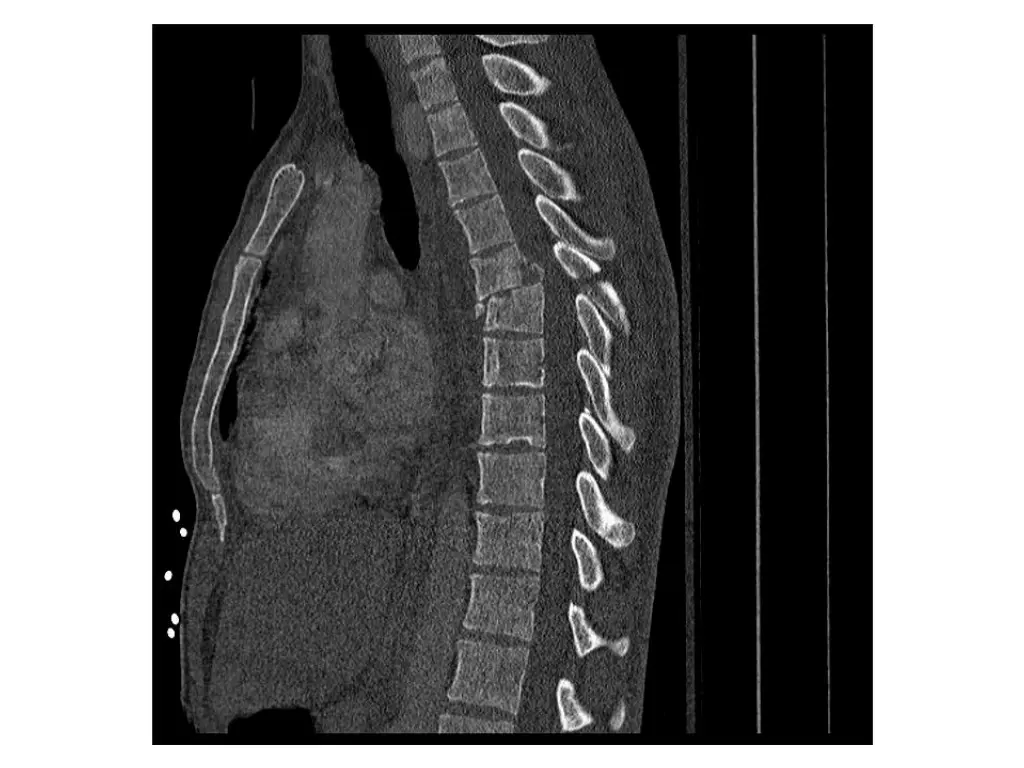

Clinical Hx (Case 3) 16 year old. Restrained rear passenger in high speed MVC wearing only lap belt. Immediate complaints of mid to low back pain. Transported to FMC. Hemodynamically stable. No LoC. Isolated injury to thoracic or lumbar spine.

Neurological exam (Case 3) Upper extremity: Sensory: Normal to light touch and pinprick Motor: 5/5 power in all muscle groups Lower extremity: Sensory: Normal to light touch and pinprick Motor: 5/5 power in all muscle groups Rectal: Sensation: Normal to light touch and pinprick Voluntary sphincter tone: Normal Other relevant findings: None

Imaging (Case 3) Lateral XR Midsagittal CT scan Parasagittal CT scan